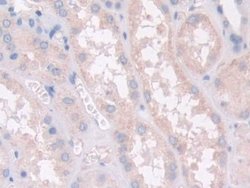

PON2 Polyclonal Antibody for Western Blot, IHC (P)

This gene encodes a member of the paraoxonase gene family, which includes three known members located adjacent to each other on the long arm of chromosome 7. The encoded protein is ubiquitously expressed in human tissues, membrane-bound, and may act as a cellular antioxidant, protecting cells from oxidative stress. Hydrolytic activity against acylhomoserine lactones, important bacterial quorum-sensing mediators, suggests the encoded protein may also play a role in defense responses to pathogenic bacteria. Mutations in this gene may be associated with vascular disease and a number of quantitative phenotypes related to diabetes. Alternatively spliced transcript variants encoding different isoforms have been described.Specifications

| Immunohistochemistry (Paraffin), Western Blot | |